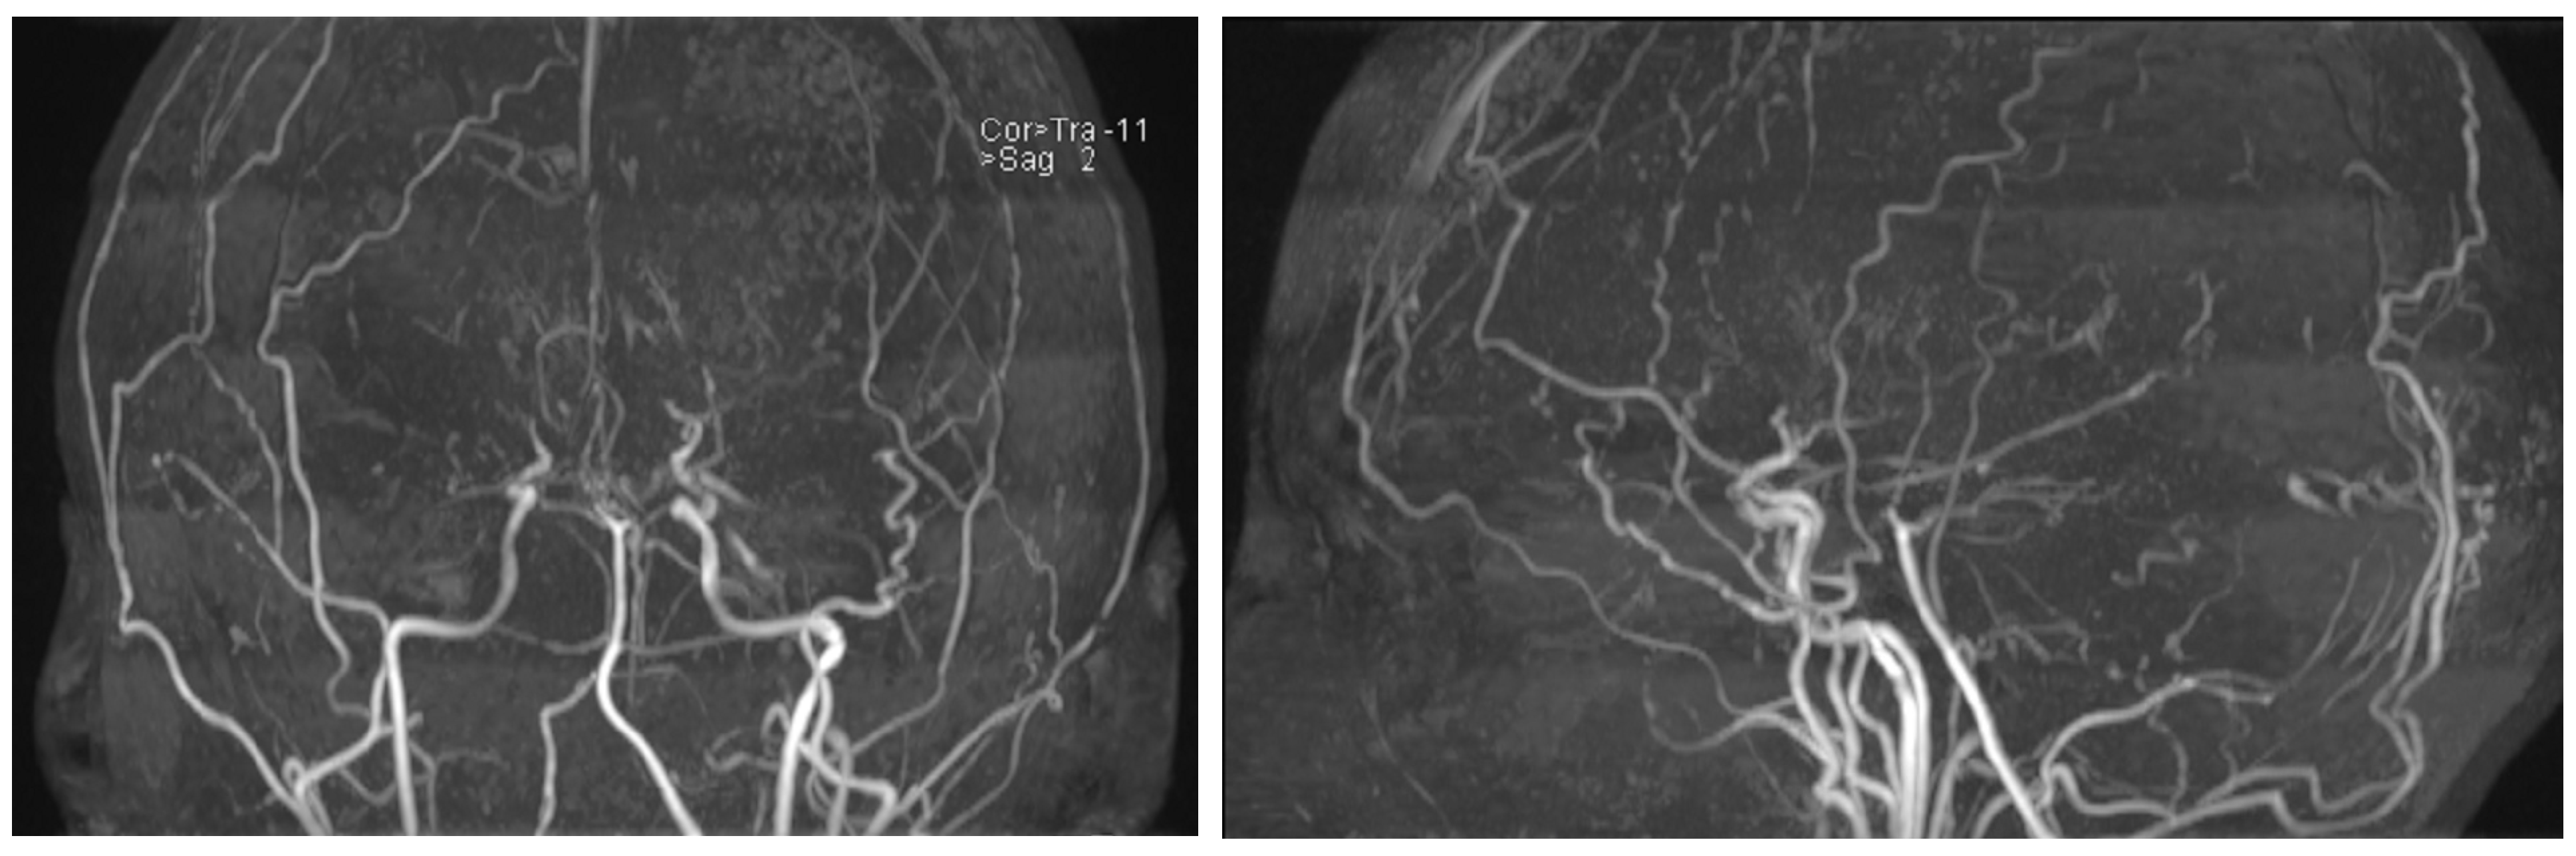

The first description of this condition dates back to 1957, when it was termed “hypoplasia of the bilateral internal carotid arteries”. Following the progressive narrowing of blood vessels of the anterior circulation, a dense collateral network of new vessels develops near the carotid apex, the cortical surface of the cerebral hemispheres, the leptomeninges, and around branches of the external carotid artery, supplying the dura mater and the skull base. Rarely, such a network may form among the vessels of the posterior circulation, namely the basilar artery and posterior cerebral arteries. The characteristic appearance of those newly formed and dilated vessels on conventional angiography was described as “hazy, like a puff of cigarette smoke” (Figure 1), which in Japanese translates to moyamoya [1,2].

Figure 1. Angiographic findings in moyamoya [1].